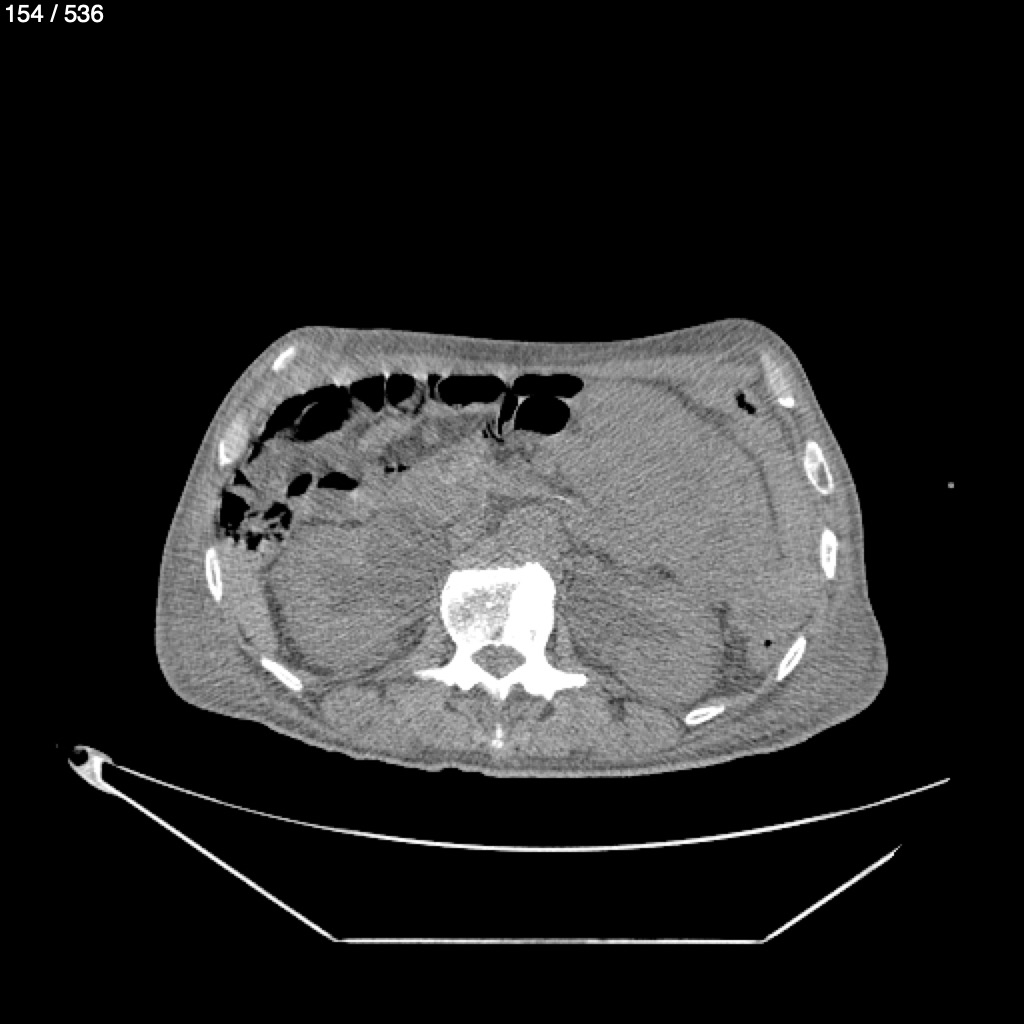

Angel Villalobos Palomeque 73 A - T.C Abdomen Simple